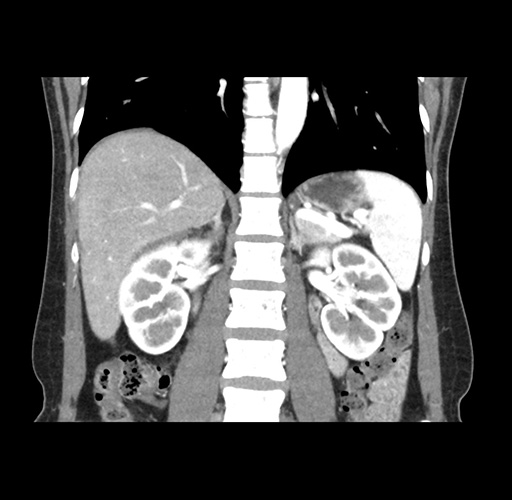

Imaging Analysis

Look through the patient's CT scan to identify any areas of concern for the necessary procedure.

Based on your CT findings, which issue(s) would give reason for "planned slowing down moment(s)" in this case?